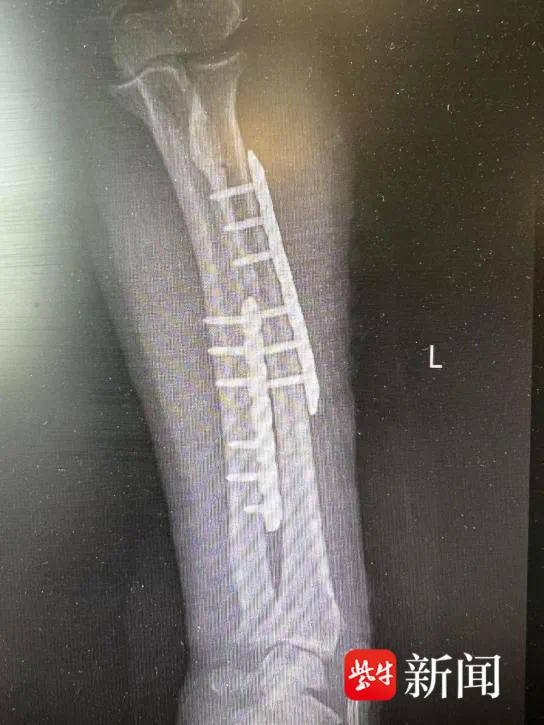

因此,等她的全身状况和伤口条件改善后,医疗团队按原定计划实施了第二阶段的功能修复手术。这次手术中,医生精细调整骨折对位,用更符合长期康复需求的内固定方式(钢板和螺钉)替代临时外固定支架,并对骨缺损部位进行植骨加固。同时,对膝关节的韧带损伤进行了针对性修复。

术后方阿姨手臂被重新接上

术后 方阿姨手臂被重新接上